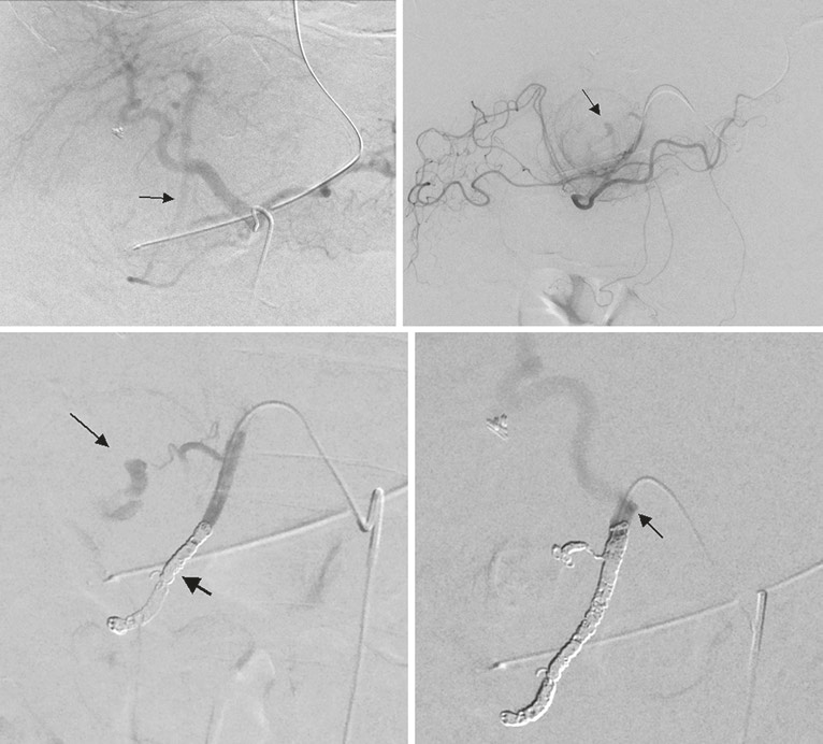

图:痔疮出血(引自苏大附二院介入科)

图:门静脉高压症